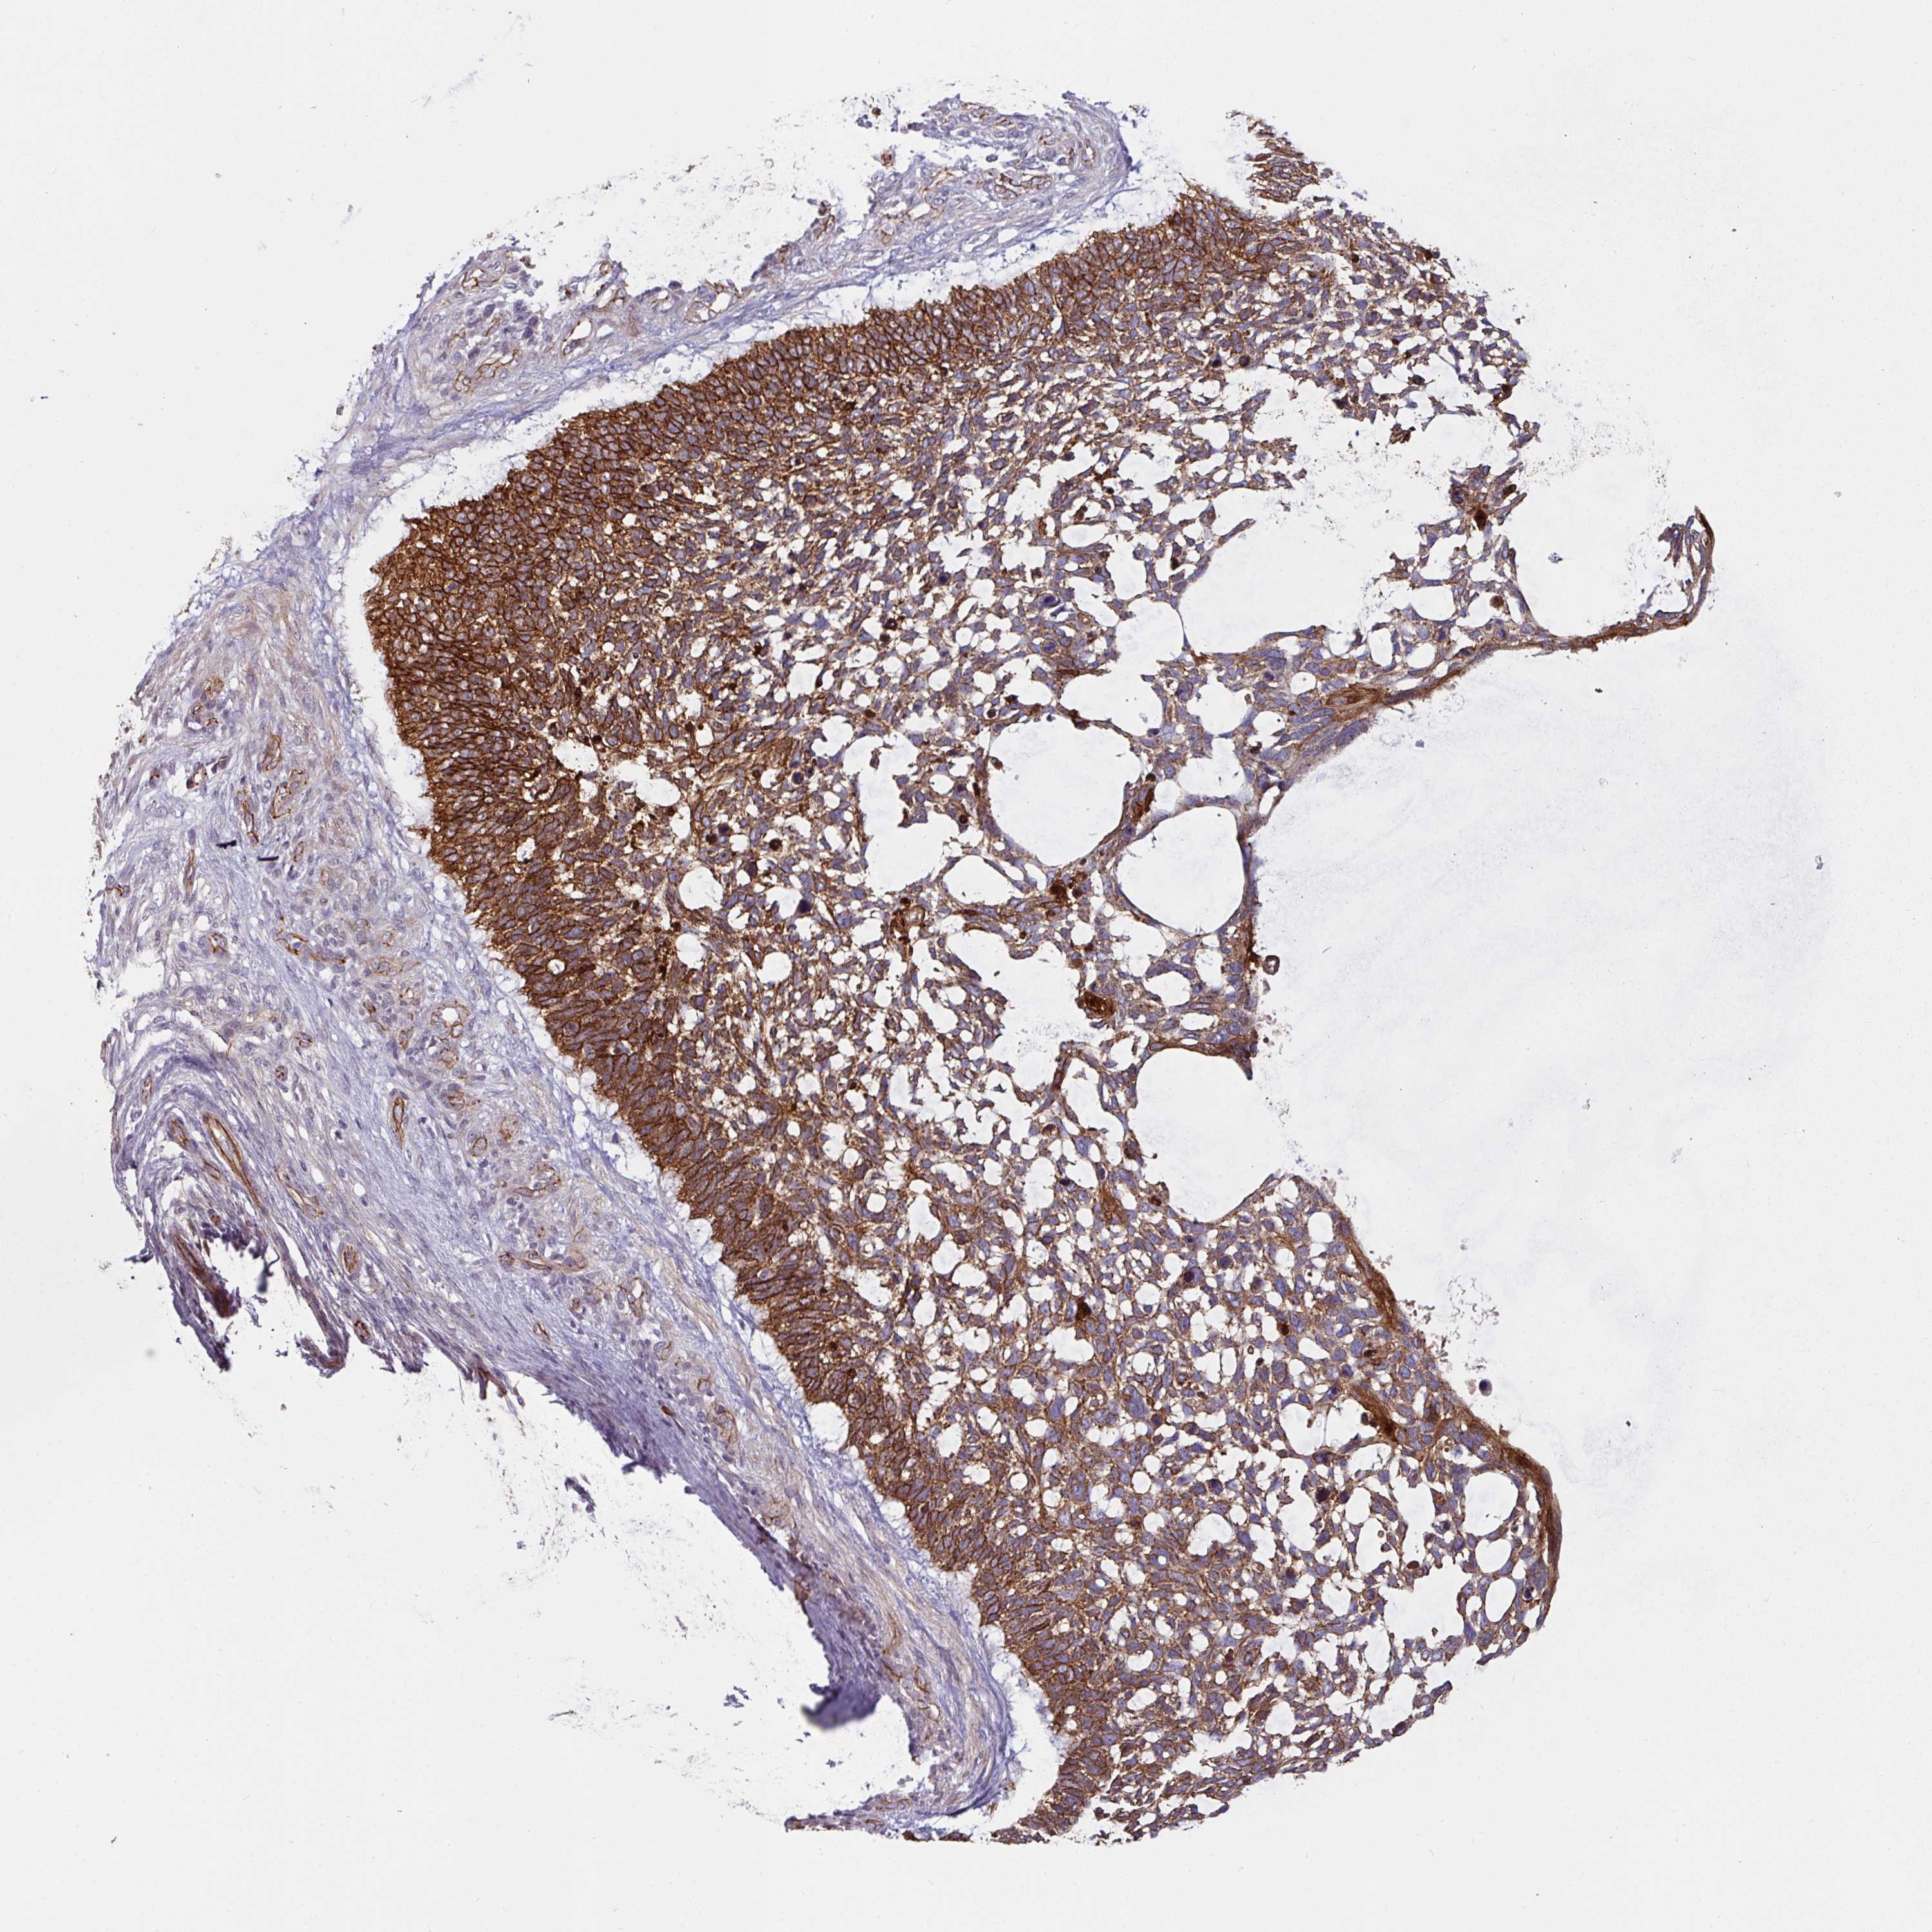

SKIN CANCER - Protein expressioni

A mouse-over function shows sample information and annotation data. Click on an image to view it in a full screen mode. Samples can be filtered based on level of antibody staining by selecting one or several of the following categories: high, medium, low and not detected. The assay and annotation is described here.

Antibody stainingi

Antibody staining in the annotated cell types in the current human tissue is reported as not detected, low, medium, or high, based on conventional immunohistochemistry profiling in selected tissues. This score is based on the combination of the staining intensity and fraction of stained cells.

Each image is clickable and will lead to virtual microscopy that enables deeper exploration of all samples and also displays staining intensity scores, fraction scores and subcellular localization as well as patient and tissue information for each sample.

Antibody HPA032047

Antibody CAB002139

Basal cell carcinoma

Squamous cell carcinoma, NOS

Squamous cell carcinoma, metastatic, NOS